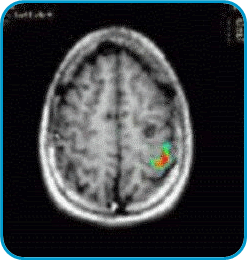

A veces es muy importante saber cuáles funciones cerebrales se encuentran en las inmediaciones de una lesión, particularmente si esa lesión va a ser extirpada quirúrgicamente. En lesiones formadas antes del nacimiento, como ciertas anomalías de los vasos sanguíneos y algunos tumores, las áreas del lenguaje y otros procesos mentales pueden estar desplazadas. La Resonancia Magnética Funcional muestra el sitio donde están localizadas estas funciones y las distancias a centros críticos de proceso mental. Por ejemplo:

En la imagen izquierda hay un pequeño quiste en el hemisferio izquierdo (nótese en el lado derecho del cerebro como un redondel negro). Esta lesión producía convulsiones. El cirujano necesitaba saber qué parte de la corteza estaba a cargo del movimiento de la mano. Con movimientos alternos de los dedos, esta imagen de resonancia magnética funcional muestra a color el área usada para el movimiento de los dedos de la mano derecha. Esto le permite al cirujano extirpar la lesión sin afectar el movimiento de la mano.